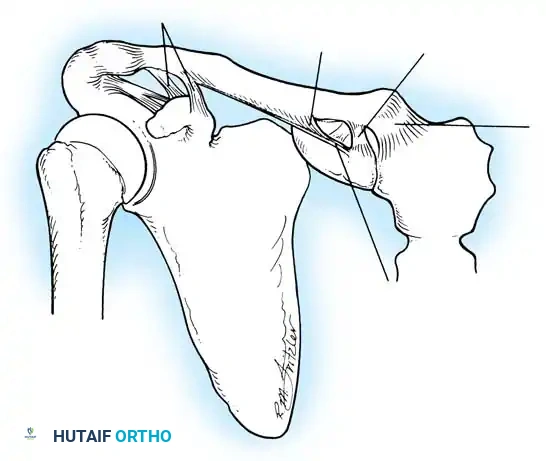

The shoulder joint capsule is inherently lax and thin, offering little resistance in isolation. However, it is reinforced anteriorly by three distinct capsular thickenings—the glenohumeral ligaments—which fuse intimately with the labral attachment on the glenoid rim. Turkel et al., alongside O’Brien, Warren, and Schwartz, have extensively mapped these structures.

- Superior Glenohumeral Ligament (SGHL): Attaches to the superior glenoid tubercle near the apex of the labrum, conjoined with the biceps anchor. It inserts onto the anterior aspect of the anatomical neck of the humerus. The SGHL is the primary restraint to inferior humeral subluxation at 0 degrees of abduction and serves as a primary stabilizer against anterior and posterior stress in the adducted arm. Harryman et al. demonstrated that tightening the rotator interval (which encompasses the SGHL and coracohumeral ligament) significantly decreases posterior and inferior translation.

- Middle Glenohumeral Ligament (MGHL): Features a wide origin extending from the SGHL along the anterior glenoid margin down to the junction of the middle and inferior thirds of the rim. It limits external rotation when the arm is in lower and middle ranges of abduction (45 degrees) but becomes redundant at 90 degrees of abduction.

- Inferior Glenohumeral Ligament (IGHL) Complex: The most critical static stabilizer. It attaches to the glenoid margin from the 2-o’clock to 3-o’clock positions anteriorly, extending to the 8-o’clock to 9-o’clock positions posteriorly. Its humeral attachment lies below the articular margin on the anatomical and surgical neck. O’Brien et al. described this complex as a "hammock-like" structure consisting of a thickened anterior band, a posterior band, and a thinner axillary pouch.

CLINICAL PEARL: The biomechanics of the IGHL complex are dynamic. With external rotation and abduction, the hammock shifts anteriorly and superiorly; the anterior band tightens to prevent anterior translation, while the posterior band fans out. Conversely, internal rotation tightens the posterior band. The anteroinferior band is the primary restraint to anterior translation at 90 degrees of abduction and external rotation (the classic apprehension position).

Turkel et al. demonstrated that true anterior dislocation cannot occur if the IGHL remains intact. Furthermore, Warren introduced the "circle concept," proving that for significant anterior translation to occur, there must be concomitant disruption or plastic deformation of the posterior capsular structures.